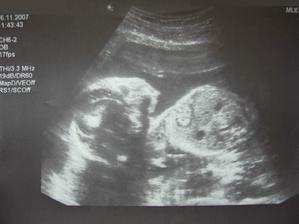

Terezka přiletí v dubnu

Týden po svatbě jsme zjistili že už měsíc pod srdíčkem mi roste nový život,byl to nejkrásnější den v životě.Ve 20.týdnu jsme byli na velkém ultrazvuku a tam nám doktor řekl, že čekáme zdravou holčičku, na kterou se moc těšíme.